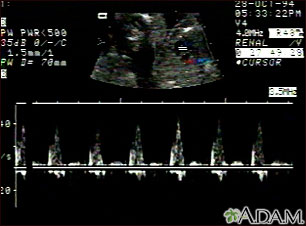

- Determine the baby's heart rate

A pregnancy ultrasound may also be done in the second and third trimesters to:

- Determine the baby's age, growth, position, and sometimes sex.